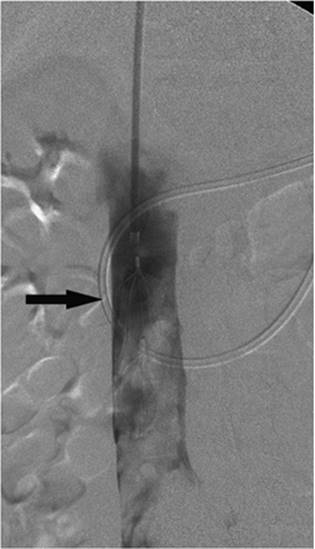

000443

Figure 35.17. On hospital day 2, internal/external drainage has been achieved by gaining access to the small intestine across the area of obstruction.

000250

Figure 35.18. This is the same patient as in Figures 35.16 and 35.17. A metallic self-expanding stent has been placed across the area of obstruction in the distal common bile duct. Note the waist in the stent (black arrow) due to the surrounding mass.